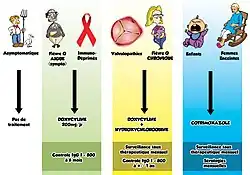

Traitement

Le traitement de la fièvre Q à sa phase aiguë avec un antibiotique est très efficace et devrait être prescrit avec l’avis d’un infectiologue. On utilise généralement les cyclines, la doxycycline, la tétracycline, le chloramphénicol, la ciprofloxacine, l’ofloxacine avec l’hydroxychloroquine. La forme chronique est plus difficile à traiter et peut nécessiter jusqu'à quatre ans de traitement avec la doxycycline et les quinolones ou la doxycycline avec l’hydroxychloroquine.

Il est particulièrement difficile de traiter la fièvre Q pendant la grossesse parce que la doxycycline et la ciprofloxacine sont contrindiquées pendant la grossesse. Le traitement à privilégier est le cotrimoxazole pendant cinq semaines[11].